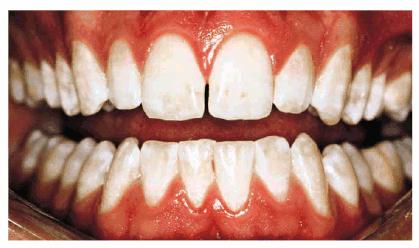

Figure 16-5: Orange-brown stain may cover more of the facial area from poor oral hygiene and ingestion of chromagenic foodstuffs.